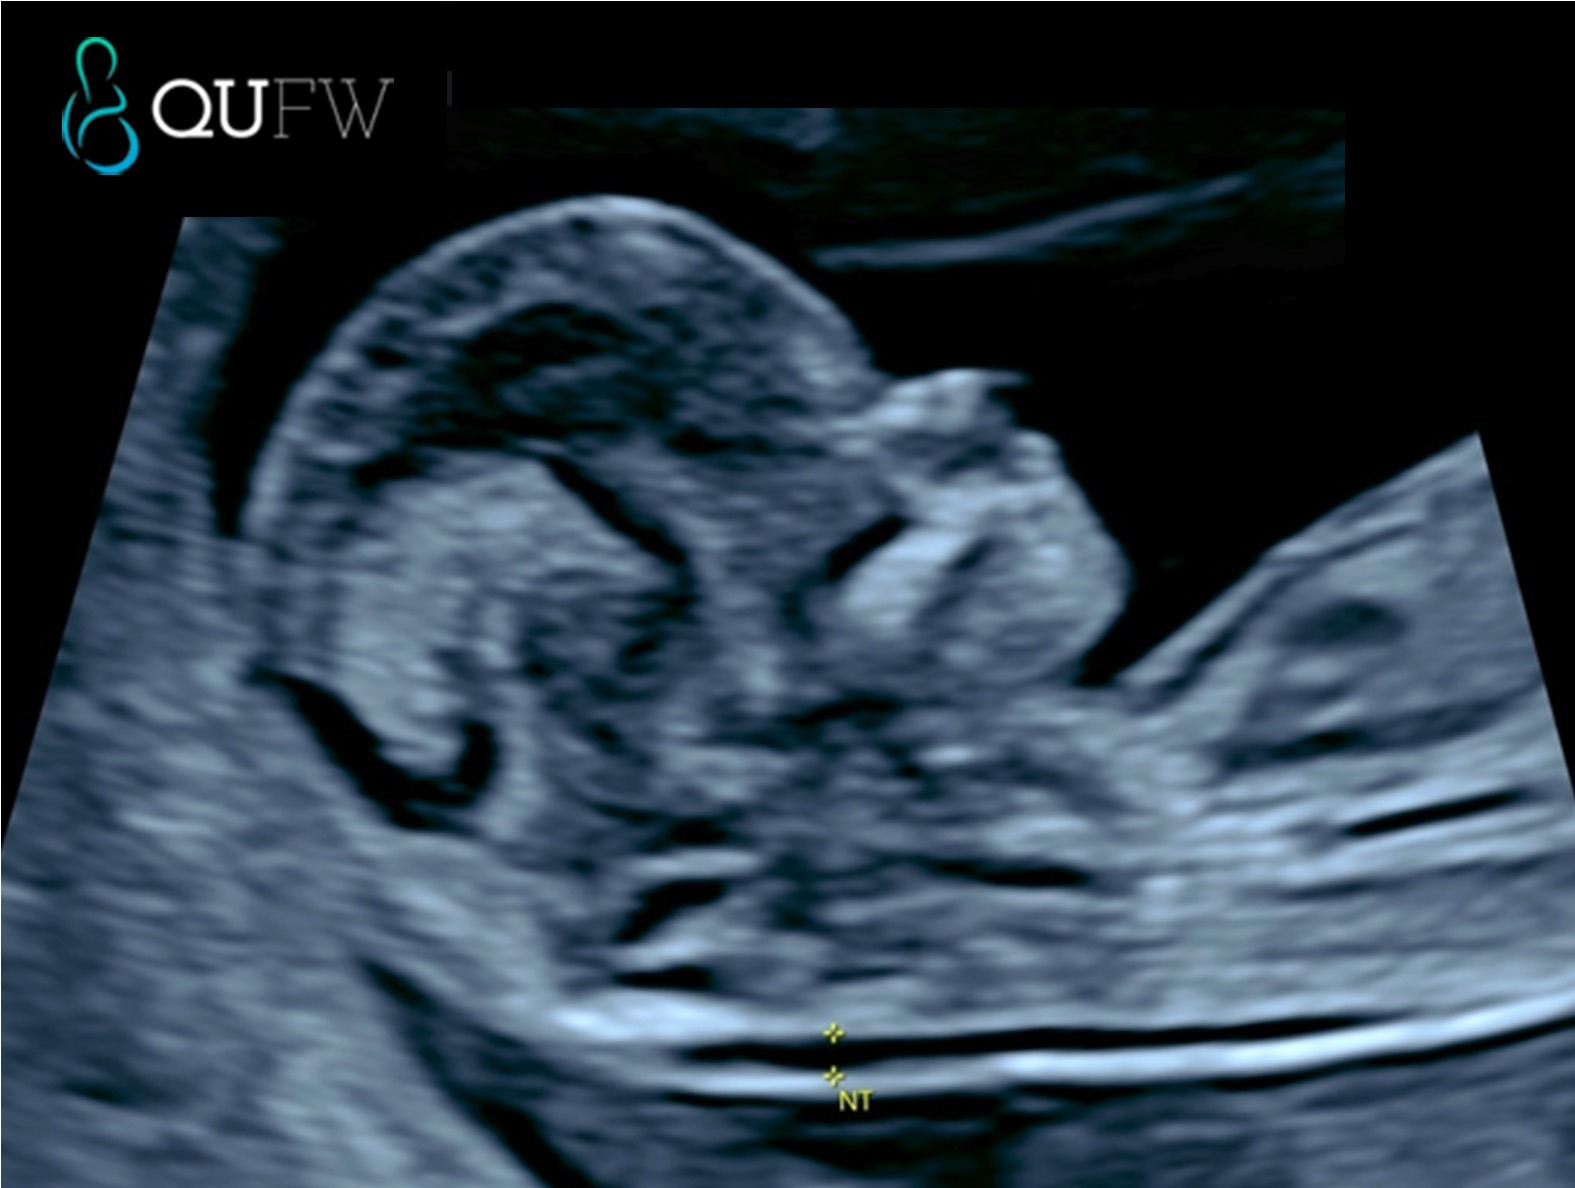

This is the same as an early anatomy scan, however we provide a risk assessment for chromosomal abnormalities like Trisomy 21, 18, and 13. As a screening for Down Syndrome, it has approx. 90% detection rate when combining the following factors such as

- Maternal age and background risk

- Ultrasound markers such as nuchal translucency, nasal bone, fetal heart rate

- Maternal serum biochemistry (Free beta-hCG and PAPP-A)

At QUFW, similar to the Early Anatomy scan we also perform a pre-eclampsia risk assessment as part of this scan.

Nuchal translucency assessment